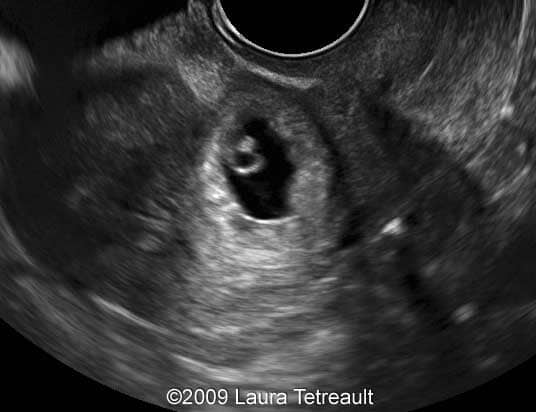

ectopic pregnancy c section scar Ectopic pregnancy in a cesarean-section scar

ectopic pregnancy scar weeks uterus obstetrics postgraduate gynecology journal sonography showing figure vaginal